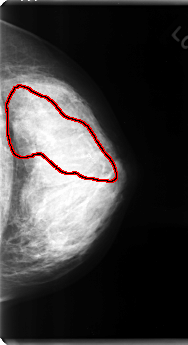

C_0120_1.LEFT_MLO

LEFT_MLO LINES 4808 PIXELS_PER_LINE 2632 BITS_PER_PIXEL 12 RESOLUTION 50 OVERLAY

FILE: C_0120_1.LEFT_MLO.OVERLAY

TOTAL_ABNORMALITIES 1

ABNORMALITY 1

LESION_TYPE CALCIFICATION TYPE AMORPHOUS-PLEOMORPHIC DISTRIBUTION SEGMENTAL

ASSESSMENT 5

SUBTLETY 5

PATHOLOGY MALIGNANT

TOTAL_OUTLINES 1

BOUNDARY